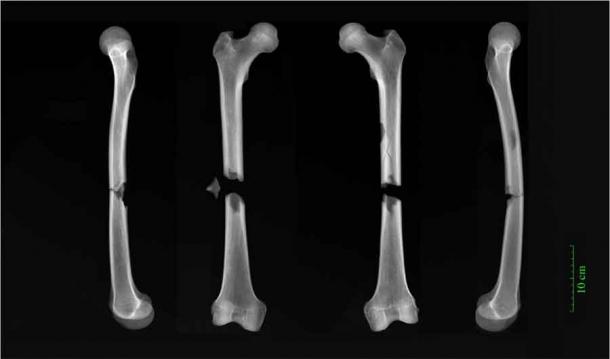

X-rays of butterfly fractures to both femora of an adult male buried in the Augustinian friary. (University of Cambridge)